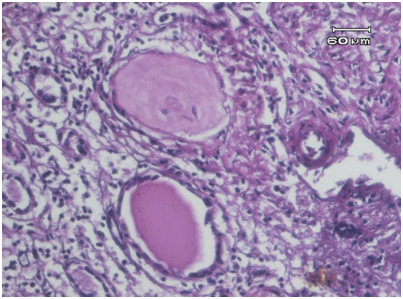

A 30 years old female with previous clinical diagnose of ovarian cyst. During the surgery they revealed that the cyst is not at the ovary but at the kidney, thus the partial nephrectomy was performed. Macroscopic examination reveals a 15x14x10cm tissues consist of multiple small cysts with brown thick septae (Figure 1). Microscopic examination shows kidney tissues with granulomatous inflammation. The glomeruli hialinated, atrophy of tubules and some with thyroidisatio (Figure 2). It also shows abundant foamy macrophages and granulomatous (Figure 3).

Figure 2 Infiltrate of inflammation cells in cortex kidney. The glomerulus hyalinization and sclerotic. One tubulus with thyroidisation.

XGP is a rare variant of pyelonephritis which is more common in women, usually affects unilateral kidney and associated with nephrolithiasis.3 There is one reported case of XGP in 40years old male with staghorn calculus but nephrolithiasis is not found in our case. Macroscopically, the affected kidneys enlarge, contain cysts formation, yellowish masses and dilated calices which can be found in our case. The destruction of affected all renal parenchyma in almost all cases which have been reported. The normal structures of kidney replaced by cystic structures as in hydronephrosis obstruction. The tipycal microscopic appearance of XGP consists of large macrophages with vacuolated sitoplasm, mononuclear inflammatory cells including plasma cells and lymphocyte. In this case we found a large number of foamy macrophage with vacuolated sitoplasm, arrange in granulomatous structures and several giant cells (Figure 4). We also found the features of classic chronic pyelonephritis which are interstitial inflammatory infiltration and tubules thyroidisation (Figure 2).2,3,7,8